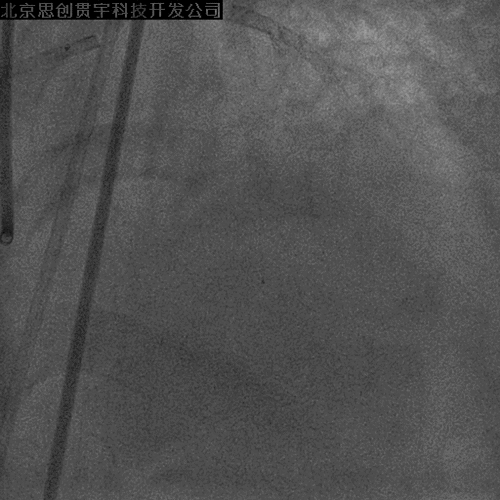

LCX开口狭窄

Finecross及双腔微导管支持下,

导丝均无法穿LM-LAD支架网眼至LCX

再次逆向掏LCX网眼

穿微导管技术( Modified Rendezvous )

球囊对吻、后扩张

POT